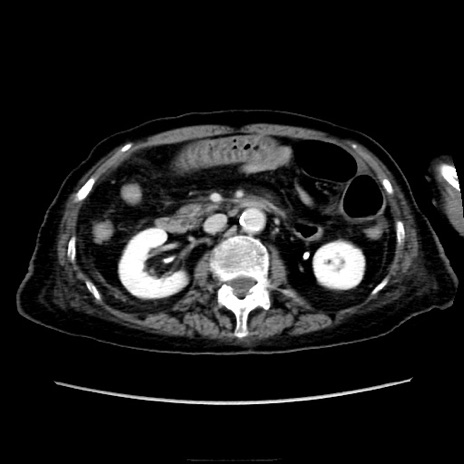

他院CT

横断像